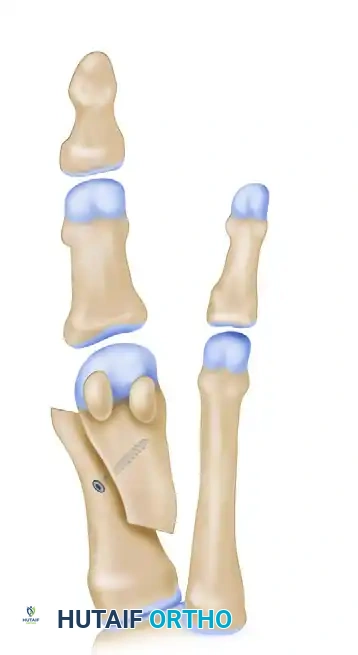

مصطلح سكارف مستمد في الأصل من مصطلحات الهندسة المعمارية وفنون النجارة، حيث يشير إلى نوع من الوصلات المتداخلة التي يتم فيها قطع نهايات قطعتين وتثبيتهما معا بحيث تتداخلان لتشكلا قطعة واحدة متصلة وقوية. في السياق الطبي، يتم تطبيق هذا المبدأ الهندسي العبقري على عظمة المشطية الأولى في القدم، حيث يقوم الجراح بإجراء قطع عظمي دقيق على شكل حرف Z.

توضيح هندسي لعملية سكارف لتقويم العظام

تتميز هذه التكوينة الهندسية بمستوى عال جدا من الاستقرار الذاتي، خاصة في المستوى السهمي للقدم، وتوفر مساحة سطحية واسعة لالتئام العظام بشكل مثالي. وقد أثبتت الدراسات الطبية والمخبرية أن عملية سكارف توفر ضعف الاستقرار الذي توفره التقنيات الجراحية الأخرى تحت ظروف تحميل الوزن، مما يجعلها الخيار المفضل للعديد من جراحي العظام المتخصصين.

تفاصيل القطع العظمي في المشطية الأولى

تنفيذ القطع العظمي على شكل حرف زي

الخطوة الجوهرية في العملية هي القطع العظمي الثلاثي على شكل حرف Z. يقوم الجراح بعمل قطع طولي في منتصف العظمة، يليه قطعان عرضيان متوازيان عند طرفي القطع الطولي. دقة هذه القطوعات حاسمة جدا، حيث تحدد مدى القدرة على إزاحة العظم وتصحيح التشوه. في التقنيات الحديثة، يوصى بأن تكون القطوعات العرضية قصيرة لتجنب اختراق الجزء الإسفنجي الضعيف من العظم.

إزاحة العظم لتصحيح الزاوية

بعد إتمام القطع، يتم إزاحة الجزء السفلي من العظم نحو الخارج لتقليل المسافة بينه وبين عظمة المشط الثانية. هذه الإزاحة هي التي تعيد الاستقامة للقدم. يتم تثبيت العظم في وضعه الجديد بشكل مؤقت باستخدام أسلاك طبية دقيقة للتأكد من المحاذاة الصحيحة.